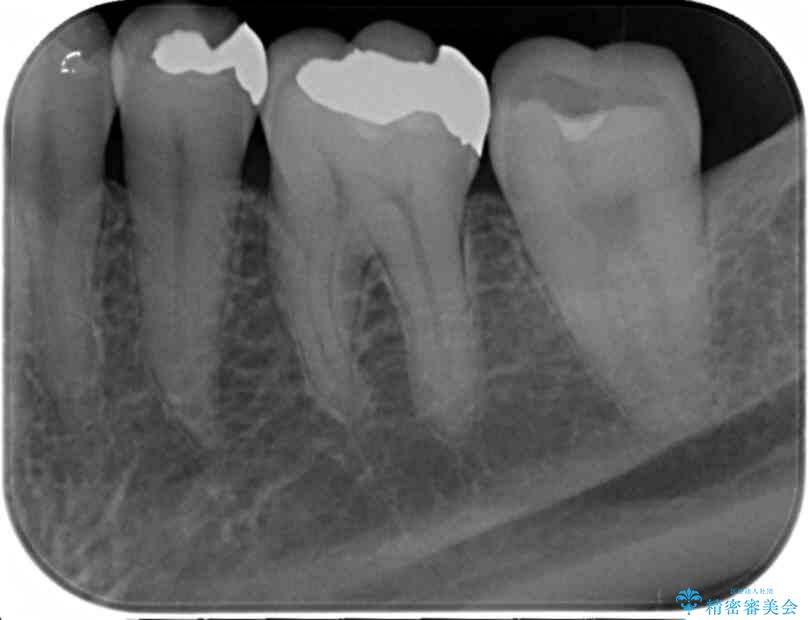

銀歯を丁寧に除去し、セラミクインレーによる置き換えを行いました。

セラミックインレーの治療に際しては、拡大鏡を用いた丁寧な除去・形成、シリコン印象材による精密な型取りを行い、虫歯の再発を防ぐような精密修復を実践していきます。